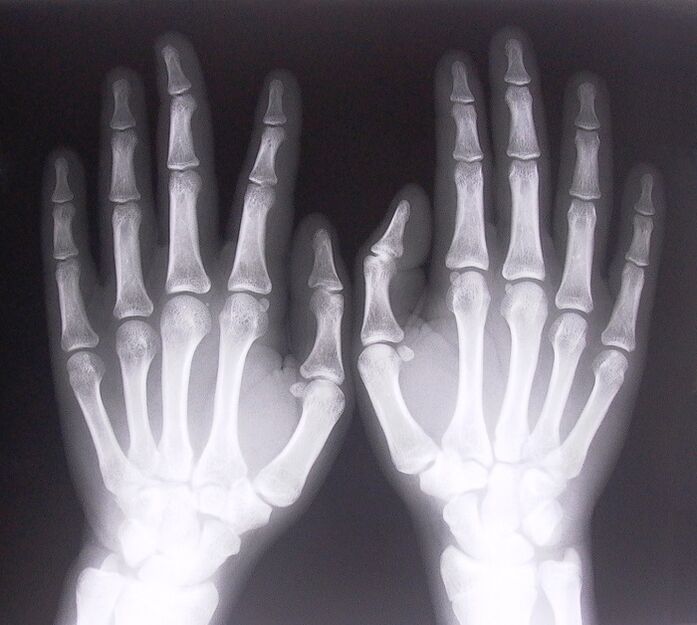

- Narrow tendonitis.To determine the cause of the disease, an X-ray is needed.Typical symptoms: pain when moving the hand, curled palm of the clenched hand.Additionally, during the renewal process, clicking sounds are often heard.

To begin treating joint pain in your fingers, you need to determine exactly what disease caused them.To determine what type of disease is causing a person to feel joint pain when bending their arms, doctors recommend performing the following procedures:

- X-ray.

- CT scan.

- Perform various blood and urine tests.

- MRI scan.

- It is necessary to check the purine content in the blood, etc.